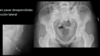

La fractura de cadera se asocia a:

- Osteoporosis - Mujeres de edad avanzada

100

Tipos de fracturas de cadera

101

¿Cómo se toma la Rx en fx de cadera?

AP y oblicua